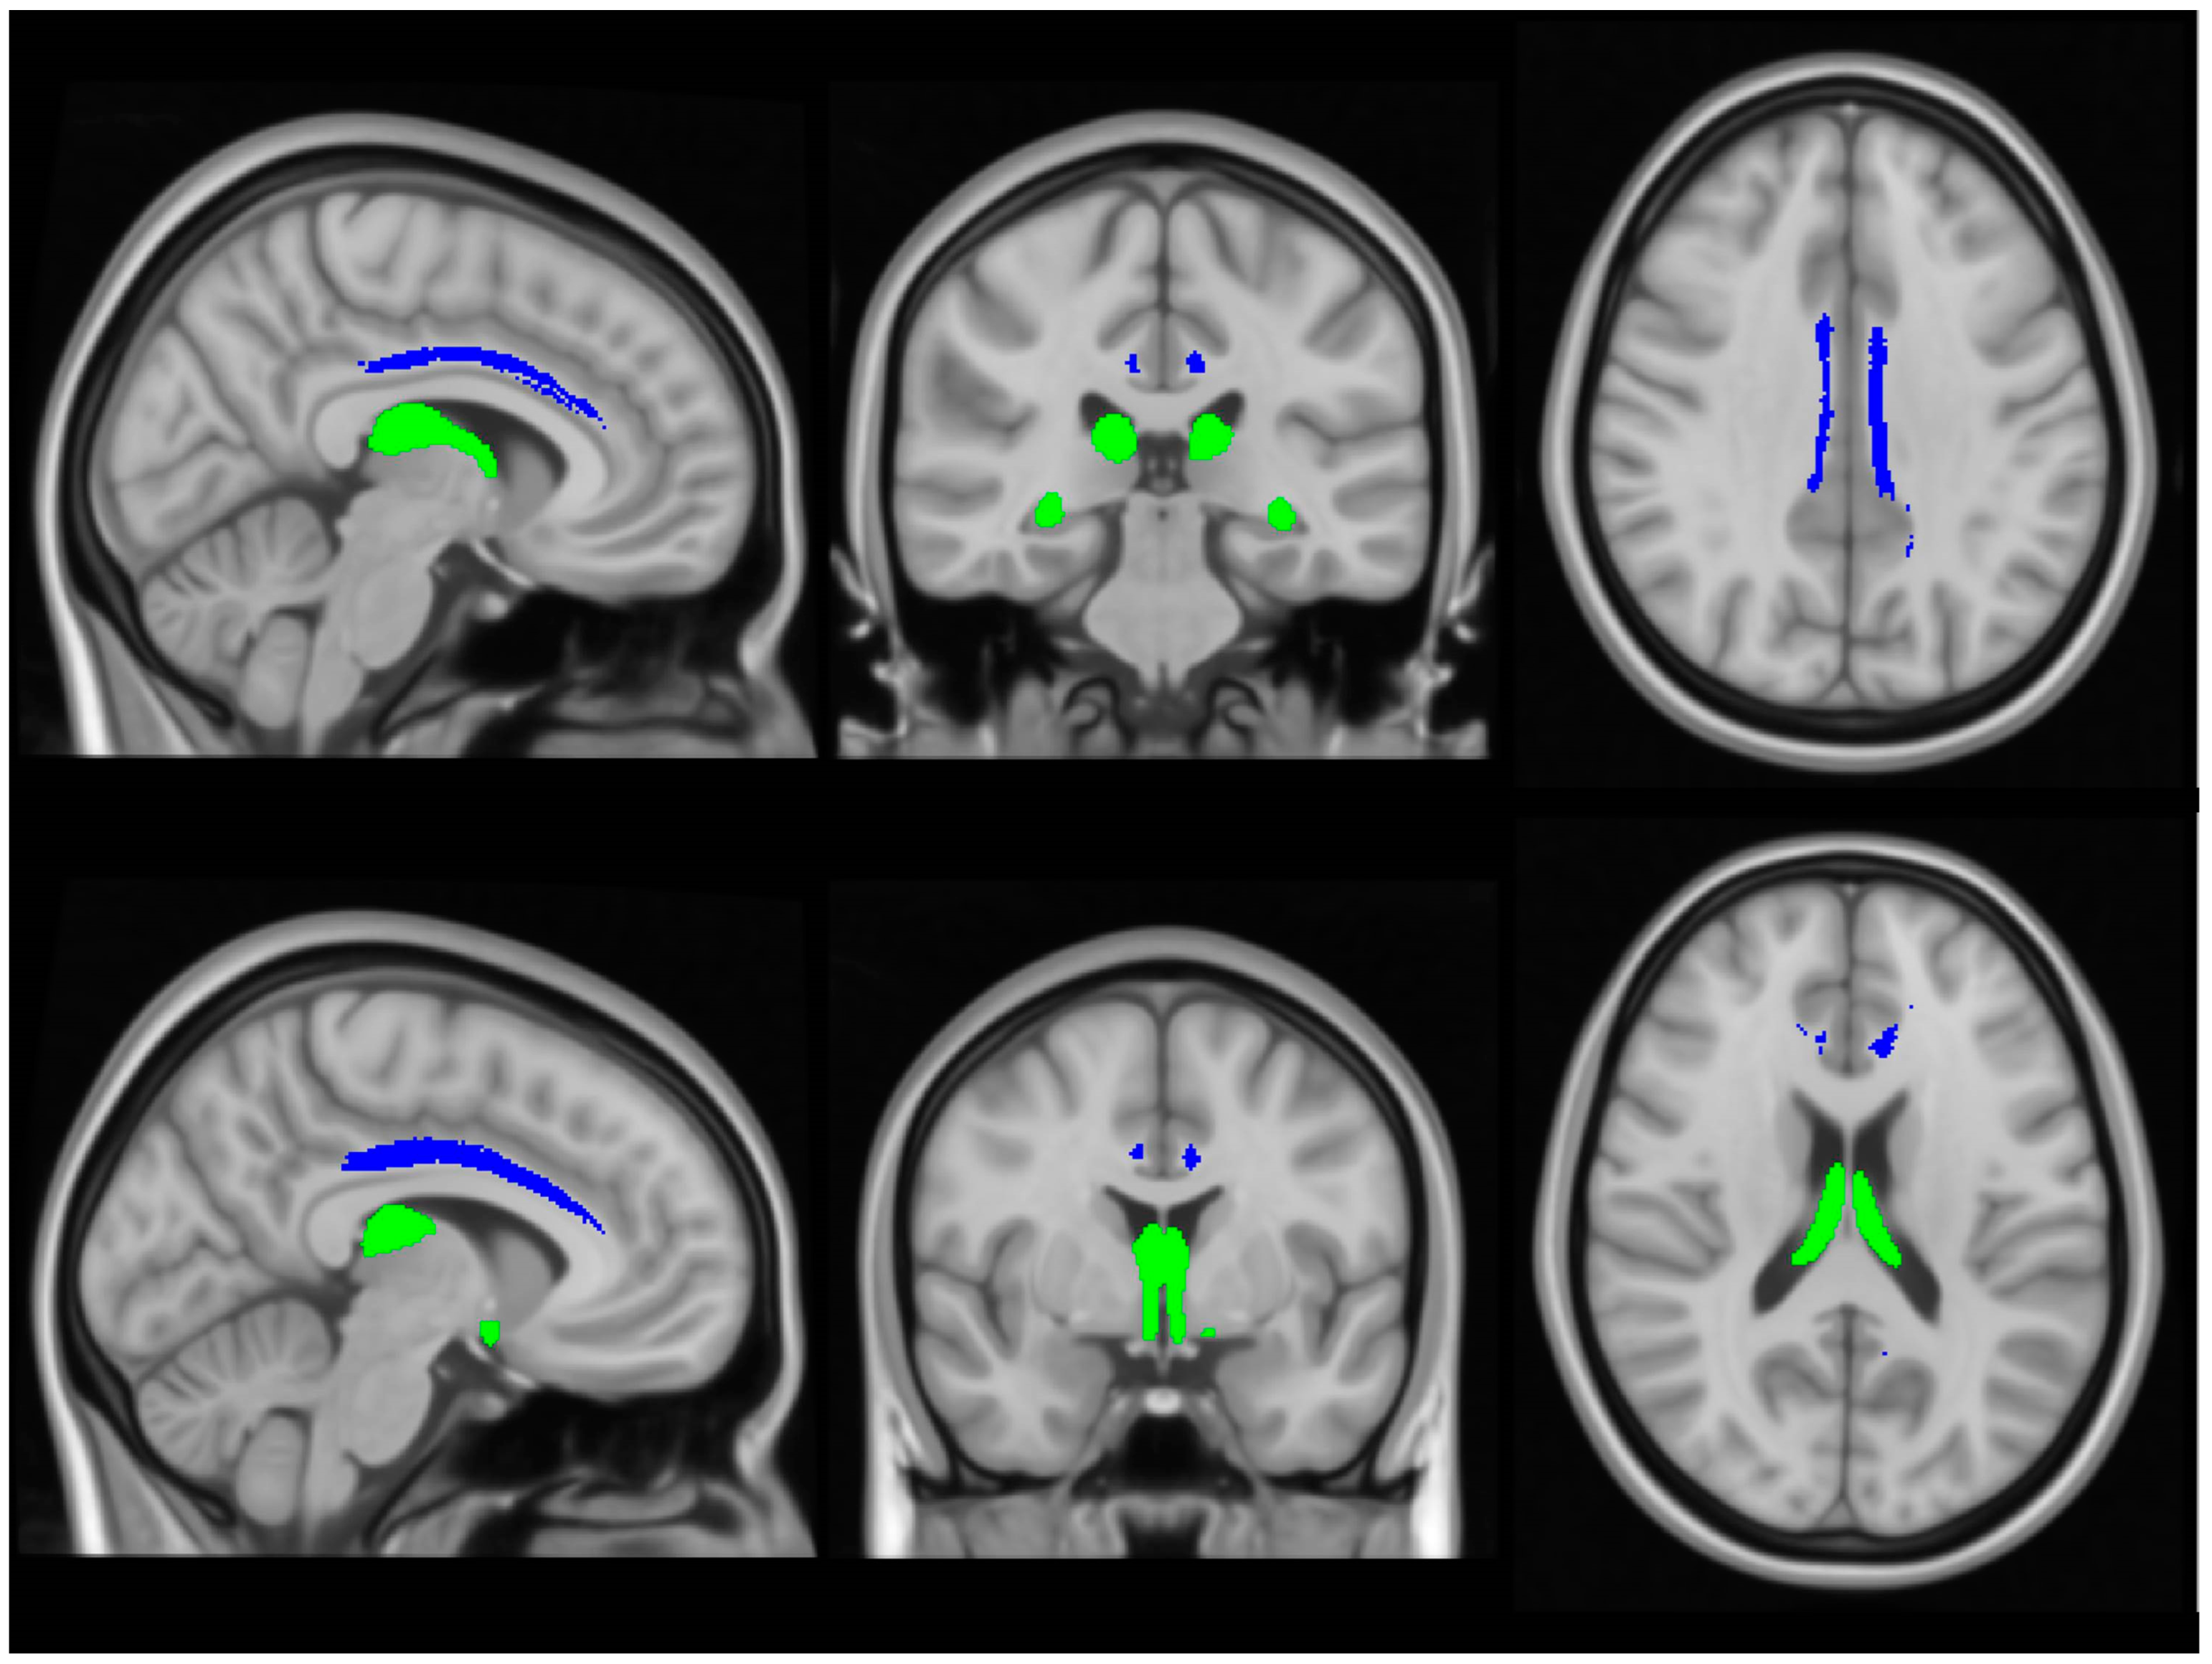

Total intracranial volumes (TIV) were estimated in FreeSurfer, implementing Buckner et al.’s approach [57]. The volumes of the left and right amygdala were retrieved from the basic pre-processing output of FreeSurfer. The subcortical limbic segmentation toolbox [58] was implemented to segment the nucleus accumbens, hypothalamus, fornix, mammillary body, basal forebrain and septal nucleus in both hemispheres separately (Figure 2). The toolbox relies on a U-Net deep-learning architecture with spatial, intensity, contrast and noise augmentation trained on 39 manually labelled data sets and extensively validated with excellent true positive rates, false discovery rates and manual–automatic volume correlations [58]. The pipeline was implemented with single T1-weighted inputs, and segmentation accuracy was individually verified in all subjects, in both patients and controls, using “freeview”. The thalamus was segmented into 25 sub-regions by a Bayesian inference pipeline implementing a probabilistic atlas developed using histological data [59], and the volumes of the left and right anterior thalamic nuclei were retrieved. The hippocampus was parcellated into cytologically-defined subfields implementing the hippocampal segmentation stream [60] of FreeSurfer to generate volumetric estimates for the left and right subiculum.

Figure 2. Deep-learning based subcortical segmentation of limbic structures, Lt: Left, Rt: Right.